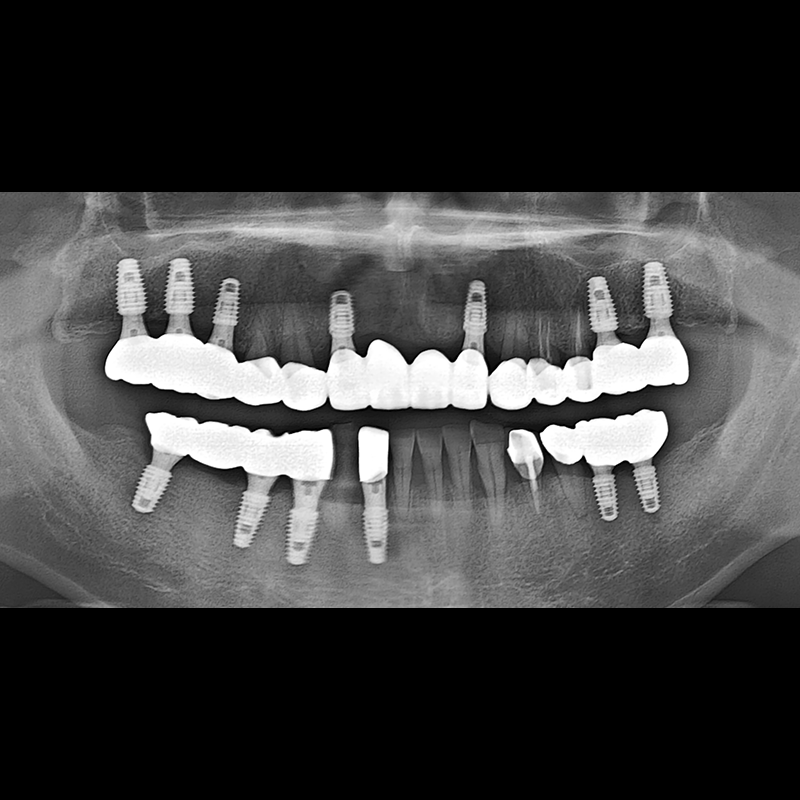

BEFORE AFTER

임플란트 전후사진 2025.05.30

결손된 치아 부분과 살리기 힘든 치아 위치에 임플란트를 식립하였습니다.